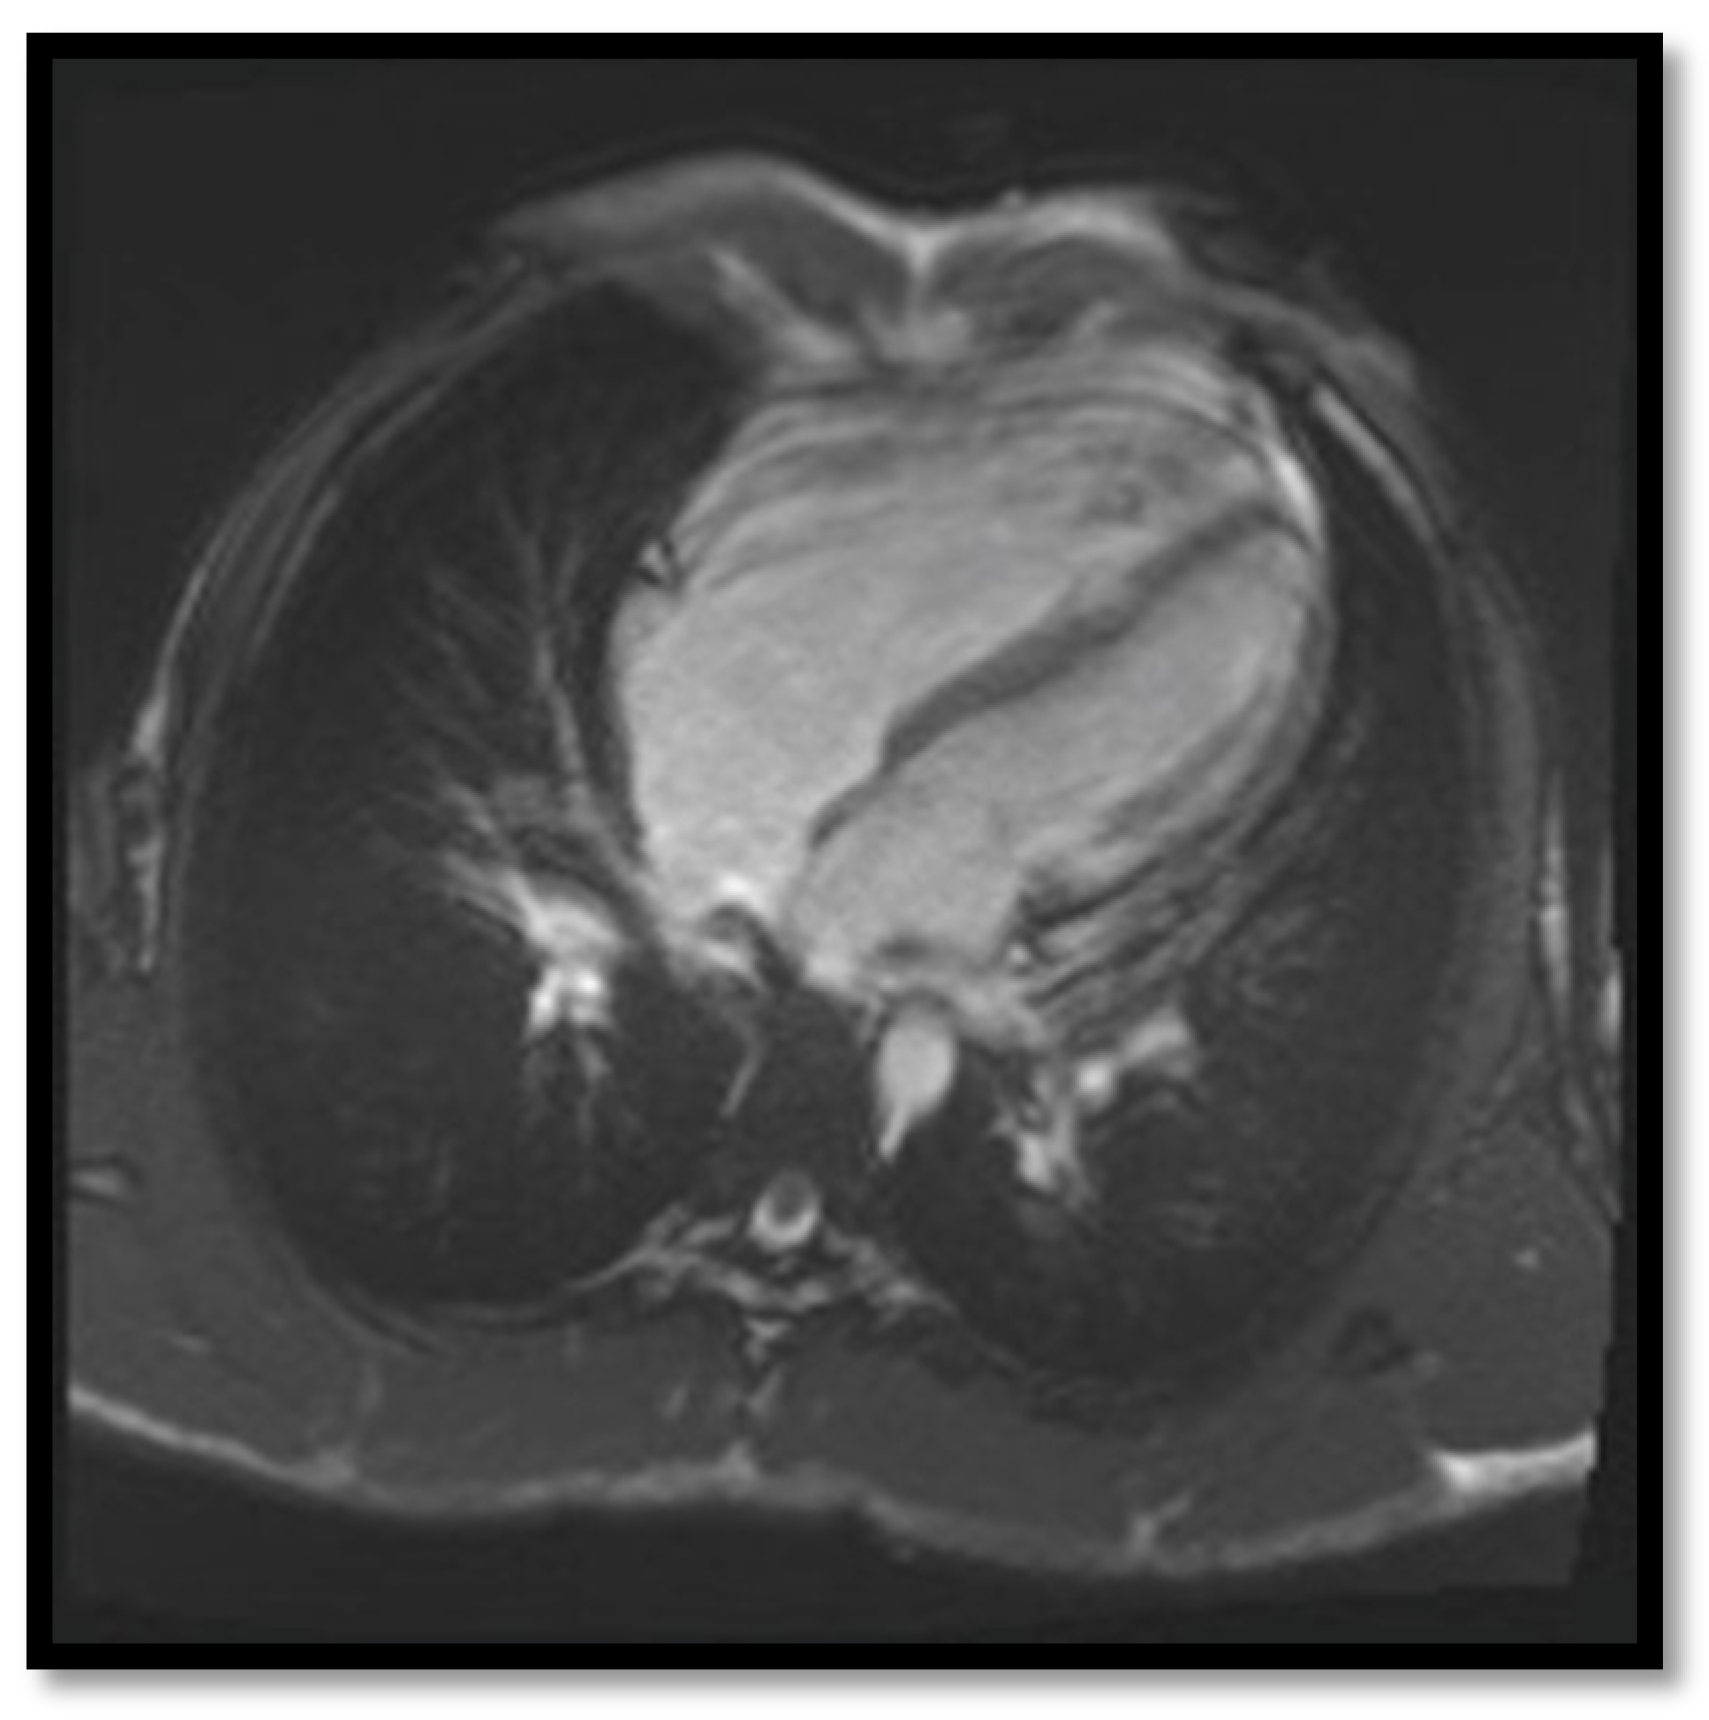

- RV dilation is also a key element for the diagnosis of ARVC. It can be segmental or global. Segmental expansion can affect only the RVOT or parts of the RV such as the basal free wall or the middle third of the free wall. It is a diagnostic criterion with high sensitivity and specificity for ARVC (Figure 3). Only the global dilation of RV is considered a diagnostic criterion for ARVC because segmental dilatation is rather difficult to interpret [12,45].